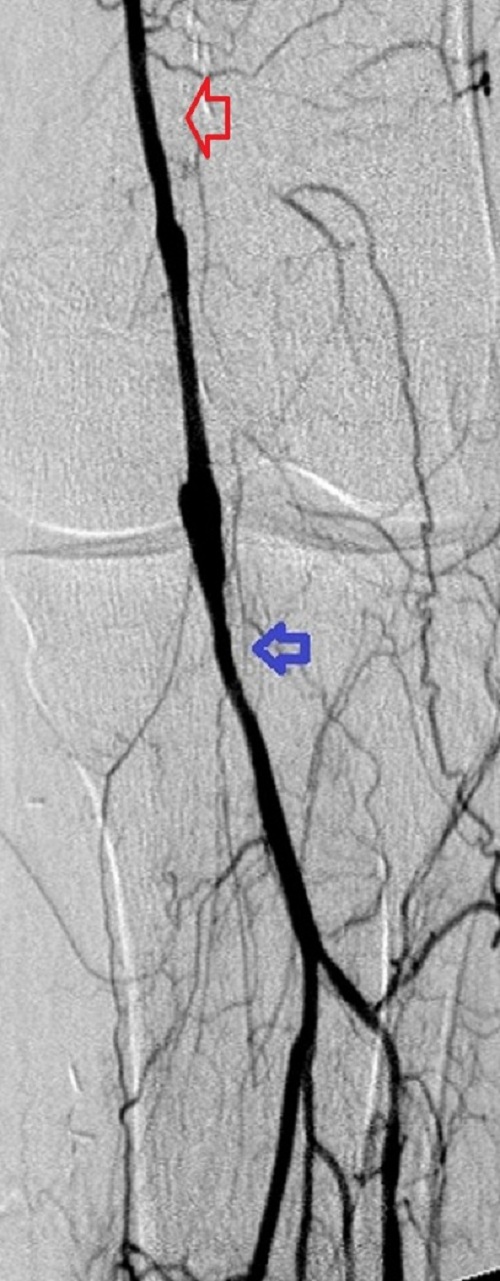

Key to images:

Top panel: Pre-intervention run-off angiogram of the left lower extremity showing, from left to right, irregular left common femoral artery (LCFA) arrowed on the 1st image, absent left superfical femoral artery (LSFA) or any bypass conduit on the 2nd image, sketchy descending collaterals from the left deep femoral (LDFA) that reconstitute a faint shadow of the left popliteal artery, arrowed on the 3rd image. The last 2 images faintly show three-vessel run-off below the left knee. The anterior tibial artery is most opacified, followed by the posterior tibial artery; the peroneal artery peeps through the upper edge of the last image. Note how weakly visible these vessels are due to the poor inflow from above.

When blood flow into or out of a bypass fails, it thromboses and its salvage includes gaining access into it and removing the clot in addition to determining the reason for its failure. Such clot removal may be mechanical, as is frequently the case in acute graft failure, or through thrombolysis, as is the case in later failures. The above images illustrate the later scenario in which the patient presented about 1 year after a left femoropopliteal bypass was fashioned for them. I crossed into the lumen of the bypass conduit from a right common femoral arterial puncture and advanced an infusion cather into it for overnight continuous alteplace infusion following a bolus dose. (I favor 5 to 10 mg of alteplace bolus, followed by continuos infusion at 0.5 mg per hour, in company with fixed unfractionated heparin infusion at 500 units to 600 units per hour after a bolus dose of 3000 units to 5000 units). In this case the bypass proved to be a vein conduit connecting the left common femoral artery, proximally, to the mid popliteal artery, distally, without intimal hyperplasia. The cause of the failure was diminished inflow due to left iliac disease.The final runoff images reveal a three-vessel tibial domain continuous with a near-normal plantar arch.